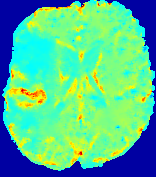

Slice #1Slice #2Slice #3Slice #4Slice #5Slice #6Dgtsuperscript𝐷gtD^{\text{gt}}Refer to captionRefer to captionRefer to captionRefer to captionRefer to captionRefer to caption(a)Refer to captionRefer to captionRefer to captionRefer to captionRefer to captionRefer to caption(b)Refer to captionRefer to captionRefer to captionRefer to captionRefer to captionRefer to caption(c)Refer to captionRefer to captionRefer to captionRefer to captionRefer to captionRefer to caption(d)Refer to captionRefer to captionRefer to captionRefer to captionRefer to captionRefer to caption(e)Refer to captionRefer to captionRefer to captionRefer to captionRefer to captionRefer to caption(f)Refer to captionRefer to captionRefer to captionRefer to captionRefer to captionRefer to captionRefer to caption000.060.060.060.120.120.120.180.180.180.240.240.240.300.300.30(mm2/s)𝑚superscript𝑚2𝑠(mm^{2}/s)

Figure 13: PIANO effectiveness and robustness testing: diffusion imaging via diffusion. Top row shows Dgtsuperscript𝐷gtD^{\text{gt}} used for simulating the ground truth pure diffusion. (a)-(f) refer to the results for D𝐷D estimated from the ground truth pure diffusion image time-series where Rician noise at levels 0%, 2%, 4%, 6%, 8%, 10% was added respectively.

Similarly, starting from the same initial condition C0superscript𝐶0C^{0} as in the ‘Advection Imaging’ experiment for each patient, we simulate concentration time-series {Cti(Ω)|i=0, 1,, 40}conditional-setsuperscript𝐶subscript𝑡𝑖Ω𝑖0140\{C^{t_{i}}\in\mathbb{R}(\Omega)|i=0,\,1,\,\ldots,\,40\} via a diffusion PDE, where we define the ground truth diffusivity D:=Dgtassign𝐷superscript𝐷gtD:=D^{\text{gt}} via the ADC map of the ISLES 2017 training set (ADC values are scaled by 0.000010.000010.00001 to ensure numerical stability):

Note this is likely not a spatially representative ground-truth for perfusion imaging, as it measures different effects from diffusion imaging. However, we still use it as a quasi-realistic pattern of diffusivity in the brain. We also added 2%, 4%, 6%, 8%, 10% levels of Rician noise to obtain simulations of ‘Diffusion Imaging’. The estimated Destsuperscript𝐷estD^{\text{est}} given concentrations of all noise levels for one patient are shown in Fig. 13, PIANO estimation results for all patients are summarized in Fig. 11 (b). Again, PIANO demonstrates its capability to recover the underlying diffusion field. In Fig. 13, when the noise level is increasing, some noisy patterns indeed appear in the associated Destsuperscript𝐷estD^{\text{est}}. Note that the ground truth diffusivity applied in this simulation experiment is about ten times larger than the diffusivity estimated in reality (Fig. 3, Fig. 4).